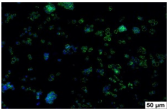

2.4. Evaluation of Macrophage Adhesion to the Surface of the Tested Samples

Following the investigation of cytotoxicity, the adhesion of macrophages to the surface of the examined samples was explored. In the experiments, it was observed that the number of adhered macrophages from the RAW 264.7 line on the surface of tablet wells without the investigated composite film materials in the microscope’s field of view was 355 ± 36 (Table 4). Upon placing RAW 264.7 cells in the tablet wells with the surface of the comparison sample “Seprafilm”, the number of adhered cells significantly decreased to 128 ± 16 within the microscope’s view field. The adhesion of macrophages on the surface of the composite film materials samples, based on the sodium salt of carboxymethylcellulose modified by allantoin (2, 3), did not differ significantly from the comparison sample “Seprafilm”.

The number of adhered cells in the microscope’s field of view was 215 ± 31 (p = 0.058) and 195 ± 29 (p = 0.064) cells, respectively. In contrast, the ability of macrophages to adhere in the samples of composite film materials based on glycoluril-modified sodium salt of carboxymethylcellulose (4, 5) was significantly lower than in sample (1) and the studied samples (2, 3). The number of adhered cells in the microscope’s field of view was 61 ± 8 and 18 ± 5, respectively.

Consequently, the tested composite film materials samples, which are based on allantoin-modified sodium salt of carboxymethylcellulose (2, 3), exhibit a diminished ability for macrophages from the RAW 264.7 line to adhere, and their adhesion value is comparable to that of sample (1).

The samples of composite film materials, derived from the glycoluril-modified sodium salt of carboxymethylcellulose (4, 5), exhibit notably reduced adhesion of RAW 264.7 line macrophages to the surface compared to both sample (1) and the examined composite film materials based on allantoin-modified sodium salt of carboxymethylcellulose (2, 3).

3.4. Adhesion of Macrophages to the Surface of the Tested Samples

Following the investigation of cytotoxicity, the adhesion of macrophages to the surface of the examined samples was scrutinized. Experimental results revealed that the number of adhered macrophages of the RAW 264.7 line on the surface of tablet wells lacking the investigated composite film materials within the microscope’s field of view was 355 ± 36 (Table 4). Upon placing RAW 264.7 cells in the wells of the tablet on the film surface of the comparison sample “Seprafilm”, the number of adhered cells significantly decreased to 128 ± 16 in the microscope’s field of view. The extent of macrophage adhesion on the surface of the samples of composite film materials based on allantoin-modified sodium salt of carboxymethylcellulose (2, 3) did not differ from sample (1), with the number of adhered cells in the microscope’s field being 215 ± 31 (p = 0.058) and 195 ± 29 (p = 0.064), respectively. The ability to adhere macrophages in the samples of composite film materials based on glycoluril-modified sodium salt of carboxymethylcellulose (4, 5) was significantly lower than in sample (1) and the studied samples (2, 3), with the number of adhered cells in the microscope’s field being 61 ± 8 and 18 ± 5, respectively.

Hence, the samples of the examined composite film materials based on allantoin-modified sodium salt of carboxymethylcellulose (2, 3) exhibit a limited ability to adhere RAW 264.7 macrophages, and their adhesion capability is not inferior to that of sample (1). In the case of samples of composite film materials based on glycoluril-modified sodium salt of carboxymethylcellulose (4, 5), the adhesion of RAW 264.7 macrophages to the surface is significantly lower compared to sample (1) and the investigated composite film materials based on allantoin-modified sodium salt of carboxymethylcellulose (2, 3).

The plates were subjected to a 24 h incubation at 37 °C in a 5% CO2 atmosphere. Following this, non-adherent cells were removed by resuspending the cell suspension. Cells attached to the surface of the composite film materials were subsequently fixed with 2.5% glutaraldehyde for 30 min and stained with fluorescent dyes, specifically Phalloidin-Atto-488 for cytoskeleton staining and DAPI for nucleus staining.

The count of cells adhered to the surface of the composite film materials within the microscope’s field of view was conducted utilizing a Leica DMi8 fluorescence microscope [40]. Three repetitions of experiments were carried out for each composite film sample and the comparison sample “Seprafilm”, with the number of adhered cells in each experiment assessed across three fields of view.